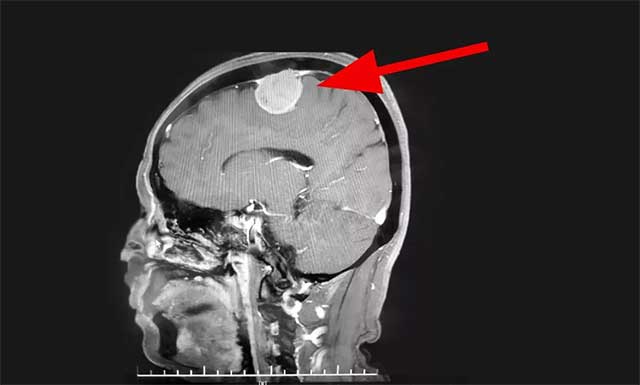

▲ 患者术前磁共振影像

医院神经外科主任沈建康教授、神经外科6A病区侯增欣主任团队在对患者完善相关检查,并开展严谨的分析评估后认为:赵女士的肿瘤位于脑部重要功能区——中央前回附近,体积较大,占位效应明显,患者手术指征明确。在明确告知患者及家属手术风险并签字确认后,由沈建康教授主刀,为赵女士行肿瘤切除手术。

术中可见,患者硬脑膜局部凸起,有明显肿瘤侵犯,硬膜动脉增粗。切开硬膜后,乒乓球大小(约4CM*4CM)的肿瘤呈灰白色,血运丰富。沈建康教授取瘤组织标本病理送检后,开始着手分块切除肿瘤。

在显微镜下,肿瘤自矢状窦向外生长,瘤体已包裹住了一支较大的皮层引流静脉。这条静脉非常重要,负责引流中央脑回的血流,必须完整保留。一旦损伤会引起静脉性水肿,严重的可导致灾难性后果——患者偏瘫甚至死亡。